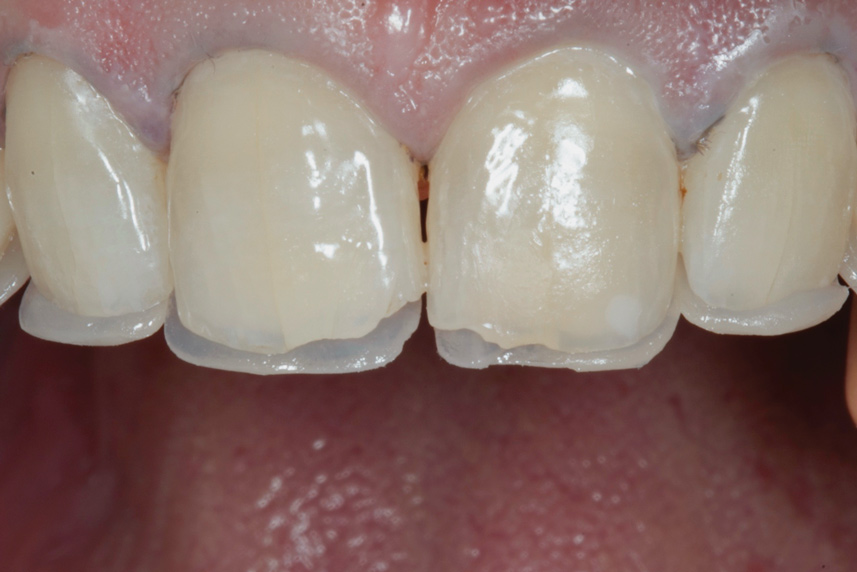

(12.) Postoperative upper anterior view.

Figure 12